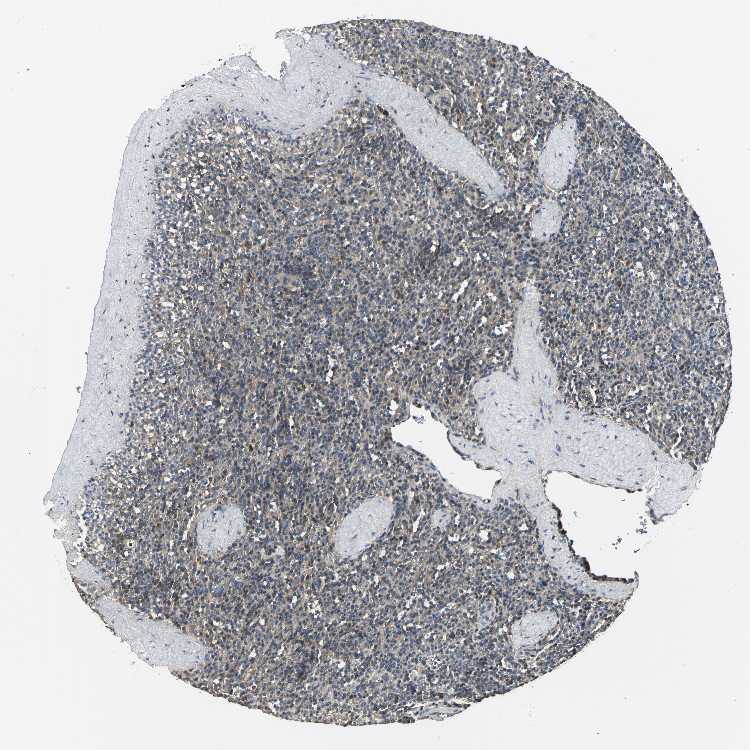

SPLEEN - Antibody stainingi

Antibody staining in the annotated cell types in the current human tissue is reported as not detected, low, medium, or high, based on conventional immunohistochemistry profiling in selected tissues. This score is based on the combination of the staining intensity and fraction of stained cells.

Each image is clickable and will lead to virtual microscopy that enables deeper exploration of all samples and also displays staining intensity scores, fraction scores and subcellular localization as well as patient and tissue information for each sample.

Antibody HPA004895Antibody CAB013018

Cells in red pulp MediumLow

Cells in white pulp MediumMedium